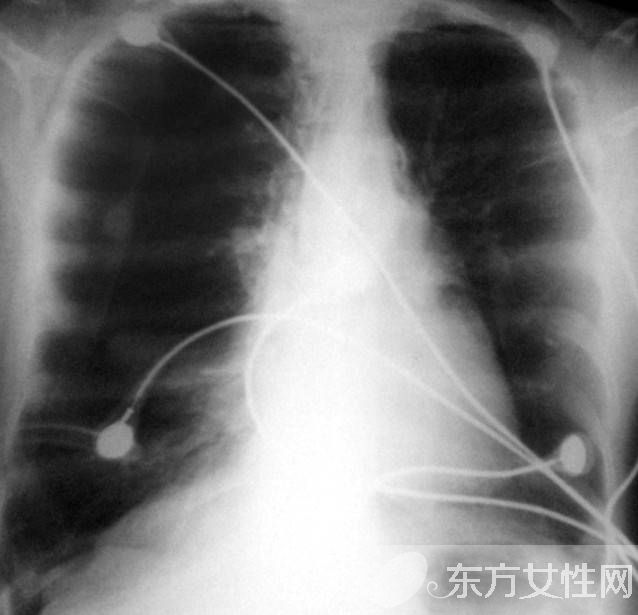

在正常的呼吸中,肺泡擴(kuò)張后收縮,使氧氣進(jìn)入血液,并且把二氧化碳排出。患上肺氣腫之后,肺泡失去彈性,為了代替,就過度擴(kuò)張,以致破裂,因而減少了氧氣的攝入量。這樣一來,心臟及頸、胸、腹部與呼吸有關(guān)或控制呼吸的肌肉必須更加用力地工作,以便攝取足夠氧氣。此外,患者的兩肺膨大,從側(cè)面看上去有桶狀胸。肺氣腫病情進(jìn)至嚴(yán)重階段,患者持續(xù)缺氧,同時(shí)過量的二氧化碳積聚在體內(nèi)?;颊唔氁柚t(yī)療措施來改善呼吸,包括使用機(jī)械輔助呼吸與面罩吸氧。最后,患者的呼吸功能可能完全衰竭。

發(fā)病緩慢,多有慢性咳嗽、咳痰史。早期癥狀不明顯,或在勞累時(shí)感覺呼吸困難,隨著病情發(fā)展,呼吸困難逐漸加重,以致難以勝任原來的工作。慢支在并發(fā)阻塞性肺氣腫時(shí),在原有的咳嗽、咳痰等癥狀的基礎(chǔ)上出現(xiàn)逐漸加重的呼吸困難。當(dāng)繼發(fā)感染時(shí),出現(xiàn)胸悶、氣急,發(fā)紺,頭痛,嗜睡,神志恍惚等呼吸衰竭癥狀。肺氣腫加重時(shí)出現(xiàn)桶狀胸,呼吸運(yùn)動減弱,呼氣延長,語顫音減弱或消失,叩診呈過清音,心濁音界縮小或消失,肝濁音界下降,心音遙遠(yuǎn),呼吸音減弱,肺部有濕啰音。部分患者發(fā)生并發(fā)癥:自發(fā)性氣胸;肺部急性感染;慢性肺源性心臟病。

輕度肺氣腫體征多無異常。肺氣腫加重時(shí)胸廓前后徑增大,外觀呈桶狀,脊柱后凸,肩和鎖骨上抬,肋間隙飽滿,肋骨和鎖骨活動減弱。語顫減弱,叩診呈過清音,心濁音界縮小或消失,肝濁音界下降。呼吸音及語顫均減弱,呼氣延長。有時(shí)肺底可聞及干濕啰音,心音遙遠(yuǎn),肺動脈第二心音亢進(jìn)。重度肺氣腫患者,即使在靜息時(shí),也會出現(xiàn)呼吸淺快,幾乎聽不到呼吸音??沙霈F(xiàn)發(fā)紺,合并肺心病右心衰竭時(shí)可出現(xiàn)頸靜脈怒張、腹水、肝大,凹陷性水腫等體征。